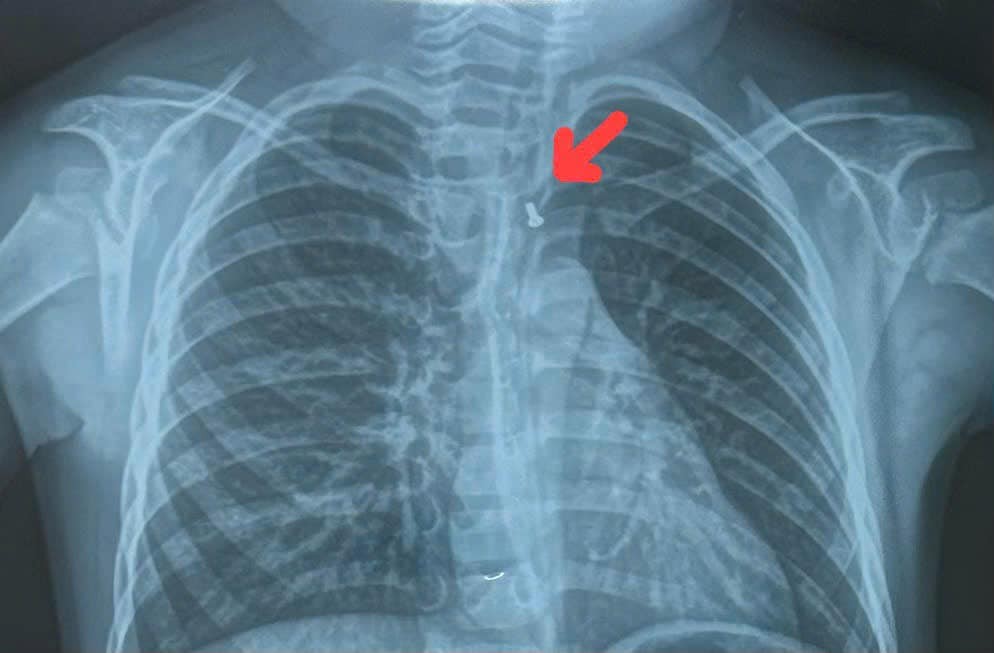

Bệnh nhi nhanh chóng được chuyển lên Bệnh viện Nhi Đồng 1 với chẩn đoán hóc dị vật. Qua kiểm tra, bác sĩ phát hiện, dị vật có hình con cá với nhiều cạnh sắc nhọn đang nằm trong thực quản bệnh nhi. Sau hội chẩn, bệnh nhi đã được bác sĩ chỉ định nội soi lấy dị vật.

Hình ảnh con cá đồ chơi bị kẹt lại trong thực quản khiến bệnh nhi không thể ăn uống được

BS Hoàng Vinh cho biết, trong quá trình nội soi, hình ảnh trên camera cho thấy dị vật là con cá nhựa dài khoảng 2cm, có nguy cơ gây tổn thương thực quản của trẻ. Ê kíp nội soi đã gắp thành công dị vật ra ngoài. Bệnh nhi may mắn khi không bị tổn thương thực quản. Sau khi lấy được dị vật, sức khỏe của trẻ đang bình phục tốt.